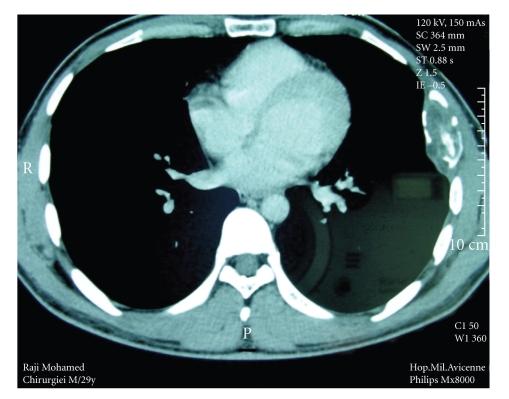

肋骨包虫囊肿:1例新病例及文献复习

The hydatid cyst is not rare in our country, but bone lesions are less common. The disease often takes the appearance of abscess or malignant lesion. We report a case of a 35-year-old man with a hydatid cyst of the rib complicated with cutaneous fistula. The surgery allowed both diagnosis and treatment. Albendazole was then administered to prevent relapse.

包虫囊肿在我国并不罕见,但骨病变较少见。该病常表现为脓肿或恶性病变。我们报告一例35岁男性,患有肋骨包虫囊肿并伴有皮肤瘘管。手术实现了诊断和治疗。随后给予阿苯达唑以预防复发。